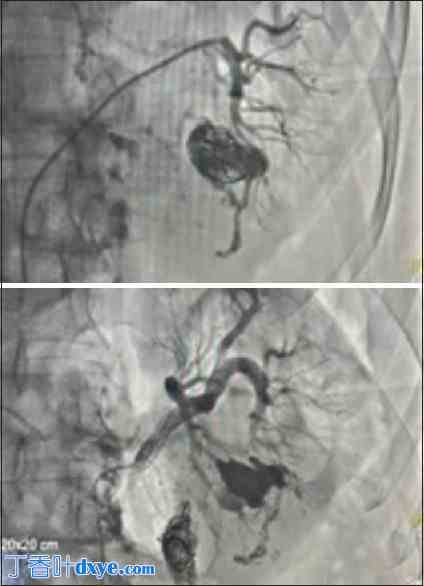

患者,67岁男性,于2023年8月因左肾结石(3 cm × 2 cm)接受左侧经皮肾镜取石术(PCNL)。术后一周,患者出现血尿,伴有血凝块排出及血凝块滞留。血红蛋白下降3 g/dL。CT血管造影显示左肾动脉主干前支有一直径2.5 cm的假性动脉瘤。患者接受选择性肾血管栓塞术,在动脉瘤腔内放置两个10 mm × 14 mm微弹簧圈,并注射2 mL 25%氰基丙烯酸酯胶(图1)。栓塞后,复查血管造影显示动脉瘤完全闭塞,所有肾内分支血供均正常。五分钟后,患者左腰部出现急性疼痛,血压升高至180/100 mmHg。荧光透视检查显示整个胶水铸型和微弹簧圈移位至肾盂输尿管连接处 (PUJ) [图1]。随后的血管造影检查显示动脉瘤再次充盈,再次用2毫升25%氰基丙烯酸酯胶进行选择性栓塞。

图1.

栓塞的假性动脉瘤腔(上图)和移位的血管内弹簧圈以及肾盂输尿管连接处的胶水(下图)